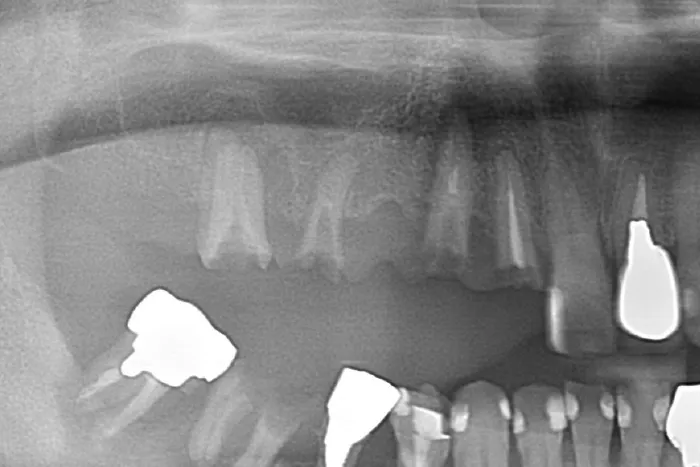

この時点から、レントゲン上でも歯槽硬線の喪失・歯石を確認できます。

定期的にレントゲン撮影を行い初期の歯周病を見落とさないようにしましょう。

レントゲン上で、軽度の骨の吸収、歯肉縁下に歯石を確認できます。

レントゲン上で、重度の骨の吸収、歯肉縁下に歯石を確認できます。

歯周病の診断を行うために、口腔内写真撮影・精密なレントゲン撮影・歯周精密検査を行います。

歯周病の診断を行うために、精密なレントゲン撮影と歯周精密検査を行います。

その上で、診断を確定させます。

この時、手指の感覚とレントゲン写真によって歯石を探知して除去します。

再度、口腔内写真・レントゲン写真・歯周病精密検査を行い治療前後の比較を行います。

ここで歯周病の改善状況を把握します。